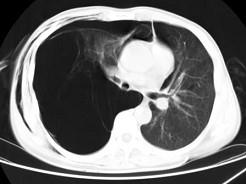

问题 男,32岁,被车撞伤后1小时,请结合影像图像选择其最可能的诊断为 ( )

选项 A、右侧肺大疱并皮下纵隔气肿 B、支气管断裂 C、右肺不张 D、右侧气胸并皮下纵隔气肿 E、右侧气胸

答案 D